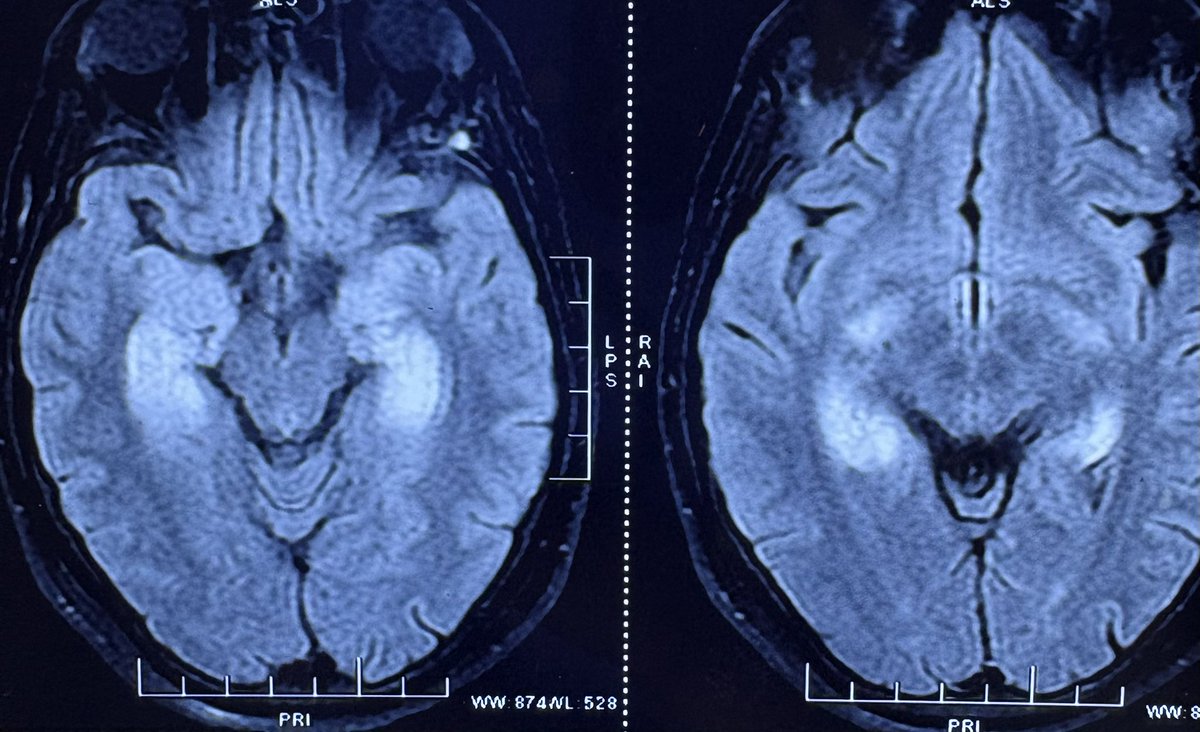

SWAN or GRE may be enough for the majority of MRI aficionados [as they require shorter acquisition times]